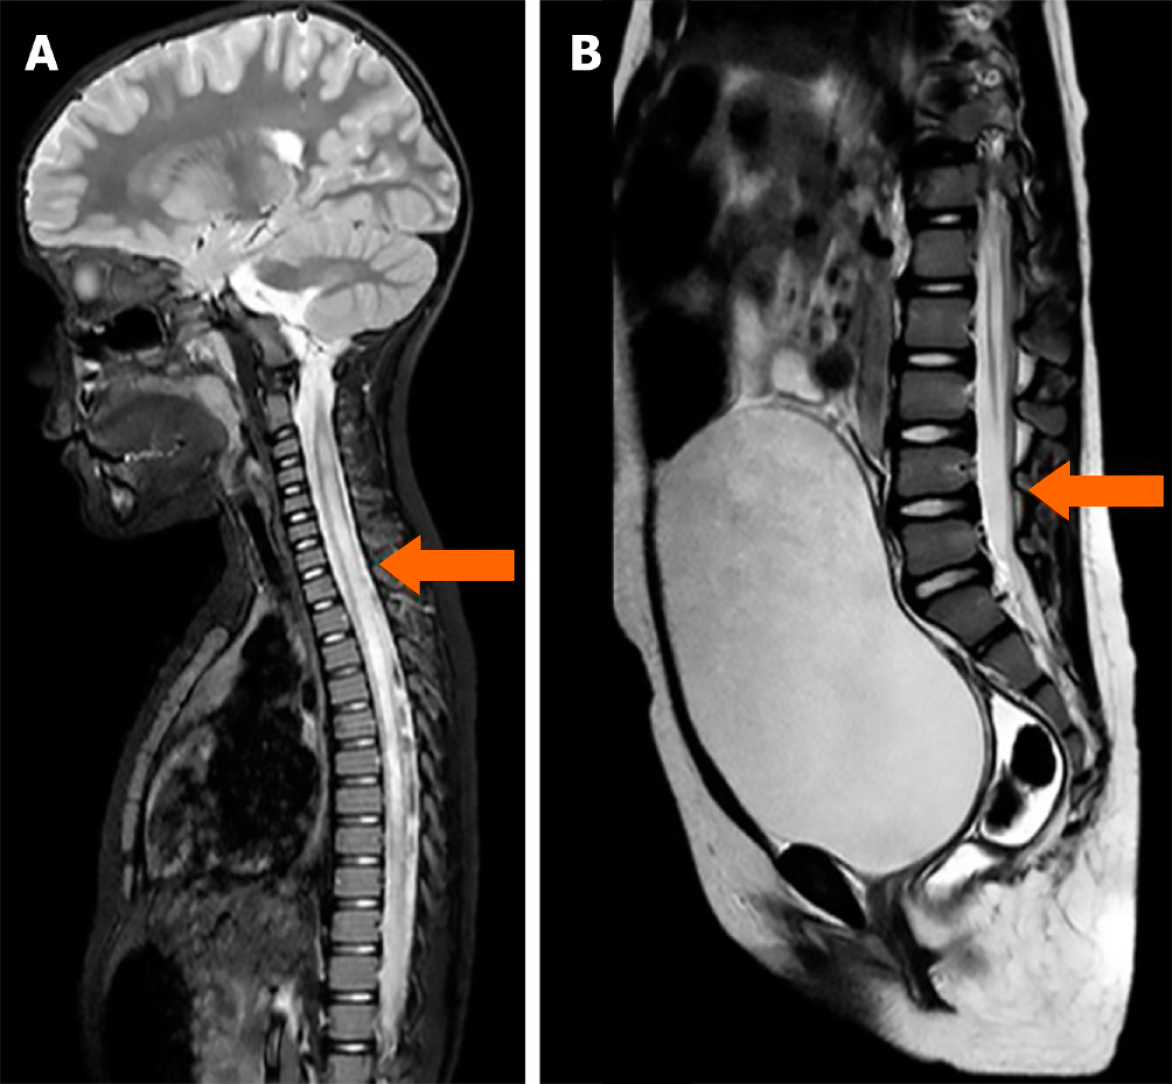

Imaging examinations

Brain and whole-spine contrast-enhanced MRI revealed a diffuse increase in spinal cord volume and an intramedullary hyperintense signal extending from C3 to the conus medullaris (Figure 1). Post-contrast imaging also demonstrated diffuse leptomeningeal enhancement.

Figure 1

Figure 1 Acute magnetic resonance imaging shows signal hyperintensities indicating transverse myelitis with longitudinal cervical and dorsal extension, extensively involving. A: The spinal cord from C3 (as indicated by the arrow); B: To the conus medullaris (as indicated by the arrow).

These imaging findings were consistent with a diagnosis of transverse myelitis with longitudinal cervical and thoracic involvement.